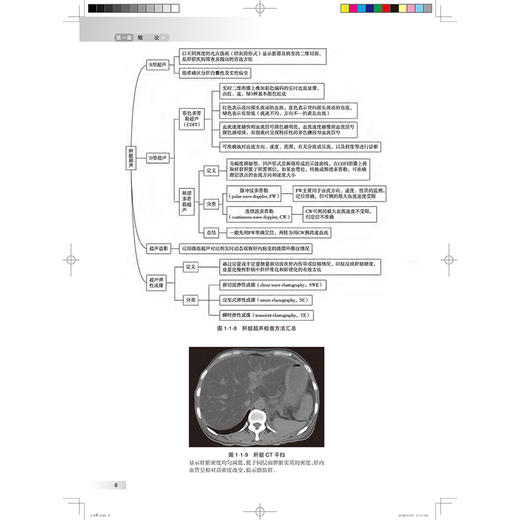

第一章 概 论/1 第一节 肝脏解剖、病理生理、疾病发病情况、影像学的价值 / 1 一、 肝脏解剖/1 二、 肝脏病理生理 / 3 三、 肝脏常见疾病的发病情况 / 3 四、 影像学的价值 / 6 第二节 胆道解剖、病理生理、疾病发病情况、影像学的价值 / 18 一、 胆道解剖/18 二、 胆道病理生理 / 20 三、 胆道系统常见疾病的发病情况/20 四、 影像学的价值 / 23 第三节 胰腺解剖、病理生理、疾病发病情况、影像学的价值 / 26 一、 胰腺解剖/26 二、 胰腺病理生理 / 27 三、 胰腺常见疾病的发病情况 / 27 四、 影像学的价值 / 29 第四节 脾脏解剖、病理生理、疾病发病情况、影像学的价值 / 35 一、 脾脏解剖/35 二、 脾脏病理生理 / 37 三、 脾脏常见疾病的发病情况 / 37 四、 影像学的价值 / 38 第五节 消化道解剖、病理生理、疾病发病情况、影像学的价值 / 42 一、 消化道解剖/42 二、 消化道病理生理 / 44 三、 消化道常见疾病的发病情况/45 四、 影像学的价值 / 46 第二章 临床症状 / 体征/54 第一节 腹痛/54 一、 腹痛的发生机制 / 54 二、 腹痛的分类及病因 / 54 三、 腹痛的临床表现 / 54 四、 腹痛的伴随症状 / 57 五、 影像学检查在腹痛诊断中的应用/57 六、 腹痛的诊断思路 / 58 第二节 腹胀/59 一、 腹胀的发生机制 / 59 二、 腹胀的分类与病因 / 59 三、 腹胀的临床表现 / 59 四、 腹胀的伴随症状 / 60 五、 腹胀的诊治思路 / 60 六、 影像学检查在腹胀诊断中的应用/61 第三节 呕吐/62 一、 定义及概述/62 二、 临床表现及诊断检查 / 63 三、 影像学在呕吐中的应用 / 63 第四节 腹泻/66 一、 定义及概述/66 二、 临床表现与诊断检查 / 66 三、 影像学在腹泻中的应用 / 67 第五节 反酸/70 一、 定义及概述/70 二、 临床表现与诊断检查 / 71 三、 影像学在反酸中的应用 / 72 第六节 嗳气/73 一、 定义及概述/73 二、 临床表现与诊断检查 / 74 三、 影像学在嗳气中的应用 / 74 第七节 吞咽困难/75 一、 定义及概述/75 二、 临床表现与诊断检查 / 76 三、 影像学在吞咽困难中的应用/77 第八节 黄疸/78 一、 定义及概述/78 二、 临床表现与诊断检查 / 78 三、 影像学在黄疸中的应用 / 79 第九节 呕血/81 一、 定义及概述/81 二、 临床表现与诊断检查 / 81 三、 影像学在呕血中的应用 / 83 第十节 便血/83 一、 定义及概述/83 二、 临床表现与诊断检查 / 84 三、 影像学在便血中的应用 / 85 第三章 肝脏影像常见征象 / 86 第一节 肝脏形态改变 / 86 一、 肝脏肿大/86 二、 肝脏缩小/91 三、 肝叶比例失调 / 94 四、 肝裂增宽/96 五、 獭尾肝/99 六、 扇贝征/101 七、 肝包膜回缩征 / 105 第二节 肝脏密度改变 / 110 一、 CT 平扫低密度 / 110 二、 CT 平扫高密度 / 115 三、 地图征/118 四、 龟背征/119 第三节 肝脏信号改变 / 120 一、 T 1WI 高信号 / 120 二、 T 1WI 低信号 / 122 三、 T 2WI 高信号 / 123 四、 T 2WI 低信号 / 125 五、 含脂病灶/127 六、 结中结/129 七、 马赛克征 / 镶嵌征 / 130 八、 门脉周围晕征 / 131 九、 簇状征/132 十、 棒棒糖征/133 十一、 靶征/135 十二、 飘带征 / 水上浮莲征 / 141 十三、 灯泡征/142 十四、 蜘蛛网征/146 十五、 轮辐征/148 十六、 繁星征/149 十七、 环礁征/151 第四节 局灶性病变强化特征 / 153 一、 速升速降/153 二、 速升缓降/156 三、 缓升缓降/160 四、 延迟强化/161 五、 环形强化/167 六、 暂时性肝脏密度 / 信号差异 / 172 七、 周边廓清征/176 八、 血管穿行征/180 九、 翻转征/184 十、 三叶草征/187 十一、 肝胆细胞期低信号 / 191 十二、 肝胆细胞期高信号 / 198 第五节 血管改变/209 一、 门静脉积气/209 二、 轨道征/211 三、 充盈缺损/212 四、 动静脉分流/214 五、 门腔静脉分流 / 217 六、 门静脉海绵样变 / 218 七、 肝静脉早显/221 八、 肝窦阻塞综合征 / 222 第四章 胆道系统影像常见征象 / 231 第一节 胆道病变/231 一、 肝内胆管扩张 / 231 二、 肝外胆管扩张 / 246 三、 肝内外胆管扩张 / 249 四、 胆管狭窄/261 五、 胆管壁增厚/268 六、 胆管肿块/275 七、 胆道积气/279 八、 剪枝征/281 九、 串珠征/282 十、 软藤征/284 十一、 杯口征/286 十二、 双管征/287 十三、 四管征/289 十四、 靶征/291 十五、 云雾征/292 十六、 中心点征/294 十七、 鸟嘴征/296 第二节 胆道病变/299 一、 胆囊肿大/299 二、 胆囊萎缩/300 三、 弥漫性胆囊壁增厚 / 302 四、 局限性胆囊壁增厚 / 305 五、 小帽征/307 六、 珍珠项链征/309 七、 瓷样胆囊/311 八、 隔膜胆囊/312 九、 双胆囊/314 十、 游离胆囊/315 十一、 高位胆囊管 / 316 十二、 低位胆囊管 / 316 十三、 胆囊窝肿块 / 319 第五章 胰腺影像常见征象 / 324 第一节 胰腺形态改变 / 324 一、 胰腺肿大/324 二、 胰腺萎缩/328 三、 胰腺局部凸起 / 332 四、 环状胰腺/336 五、 哑铃形胰腺/337 六、 分叶胰腺/338 七、 胰腺分裂/339 八、 腊肠征/340 九、 胶囊征/341 第二节 胰腺密度改变 / 343 一、 CT 平扫低密度 / 343 二、 CT 平扫高密度 / 349 三、 钙化/353 第三节 胰腺信号改变 / 359 一、 T 1WI 高信号 / 359 二、 T 1WI 低信号 / 365 三、 T 2WI 高信号 / 376 四、 T 2WI 低信号 / 386 第四节 胰管改变/398 一、 胰管扩张/398 二、 胰管狭窄/402 三、 胰管穿行 / 穿透征 / 402 四、 胰管截断征/402 五、 胰管串珠征/404 六、 胰管不相交征 / 405 第五节 肿块/406 一、 富血供肿块/406 二、 乏血供肿块/409 三、 囊性肿块/413 四、 囊实性肿块/419 五、 葡萄征/423 六、 蜂窝征/424 七、 血管穿行征/427 八、 包膜征/430 九、 浮云征/433 第六章 脾脏影像常见征象 / 437 第一节 脾脏形态改变 / 437 一、 脾肿大/437 二、 脾皮质边缘征 / 439 三、 脾楔形不强化区 / 441 第二节 脾脏信号密度特征 / 443 一、 花斑脾/443 二、 脾脏密度增加 / 444 三、 岩石脾/445 四、 脾裂隙征/447 五、 脾包膜钙化/448 六、 T 2WI 灯泡征 / 449 七、 脾气泡征(气 - 液平面) / 452 第七章 食管影像常见征象 / 456 第一节 食管管腔改变 / 456 一、 管腔狭窄/456 二、 管腔扩张/458 三、 鸟嘴征 / 萝卜根征 / 460 四、 三环征/462 五、 腔内异常/463 第二节 管壁改变/465 一、 管壁隆起/465 二、 管壁凹陷/467 三、 管壁增厚/470 四、 管壁僵硬/472 五、 充盈缺损/474 六、 龛影/476 七、 憩室/478 第三节 黏膜改变/480 一、 黏膜破坏/480 二、 黏膜平坦/481 三、 黏膜增宽和迂曲 / 483 四、 环形征/485 第四节 腔外改变/487 一、 食管压迹/487 二、 脂肪间隙异常 / 490 三、 管壁外积气/492 第八章 胃影像常见征象 / 495 第一节 胃腔改变/495 一、 胃腔扩张/495 二、 胃腔缩小/498 三、 葫芦形胃 / 哑铃形胃 / 503 四、 皮革胃/504 五、 胃扭转/506 六、 双泡征/508 第二节 胃壁改变/510 一、 胃壁隆起/510 二、 胃壁凹陷/515 三、 胃壁增厚/518 四、 胃壁僵硬/527 五、 胃壁积气/531 六、 胃壁水肿/532 七、 胃壁肿块/534 八、 龛影/536 九、 充盈缺损/539 十、 憩室/541 第三节 黏膜改变/544 一、 黏膜破坏/544 二、 黏膜平坦/546 三、 黏膜增宽和迂曲 / 547 四、 黏膜纠集/549 第四节 其他改变/550 一、 半月征/550 二、 狭颈征/552 三、 项圈征/554 四、 指压征 / 裂隙征/555 五、 环堤征/557 六、 肩胛征 / 袖口征/560 第九章 肠管影像常见征象 / 565 第一节 肠腔改变/565 一、 肠腔扩张/565 二、 动脉瘤样扩张 / 567 三、 肠腔狭窄/568 四、 肠腔高密度/571 五、 靶环征/572 六、 鹅颈征/574 七、 苹果核征/575 八、 铅管征/577 九、 咖啡豆征/578 十、 鸟嘴征/580 十一、 堆硬币征/581 十二、 哨兵袢征/584 第二节 肠壁改变/587 一、 肠壁增厚/587 二、 肠壁肿块/595 三、 肠壁气体/601 四、 分层强化(三明治征)/604 五、 肠壁憩室/606 六、 肠壁囊性 / 囊实性病变 / 608 七、 肠壁穿孔/611 八、 肠壁溃疡/614 九、 指压痕征(缺血坏死性肠炎)/616 十、 鹅卵石 / 铺路石征 / 617 第三节 肠系膜改变 / 620 一、 梳齿征/620 二、 漩涡征/623 三、 肠系膜混浊征 / 626 四、 缆绳征/629 五、 肠系膜污垢征 / 630 六、 结肠旁高密度环征(肠脂垂)/632 七、 脂肪晕征/634 八、 手风琴征/635 九、 腹茧症/638 十、 脂肪条纹征/641 十一、 脂肪环征/643 中英文名词对照索引/646 登录中华临床影像征象库步骤 / 650